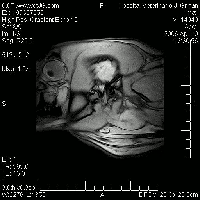

Neuroanatomía | |||||||||||||

VII |

II , III , IV , V, VI |

V, VII |

IX,X, XI, XII |

V, VII, VIII |